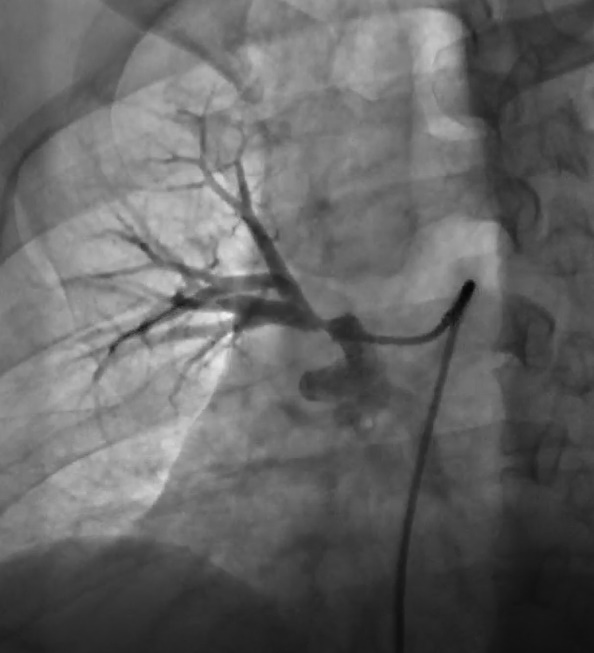

首先选择性肺动脉造影:显示右上肺动脉开口处严重狭窄。